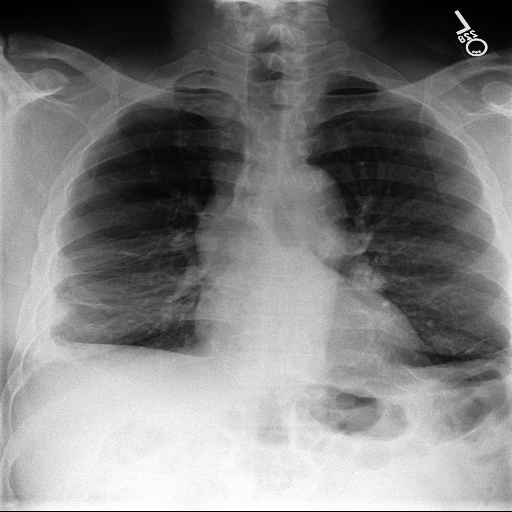

Refer to caption

Figure 3: Example of a cancerous chest X-ray and linked radiology report from the MIMIC-CXR dataset. Clinical concepts extracted (‘Nodule’) are highlighted by bounding box. Note the negative mention in the final paragraph is not extracted.